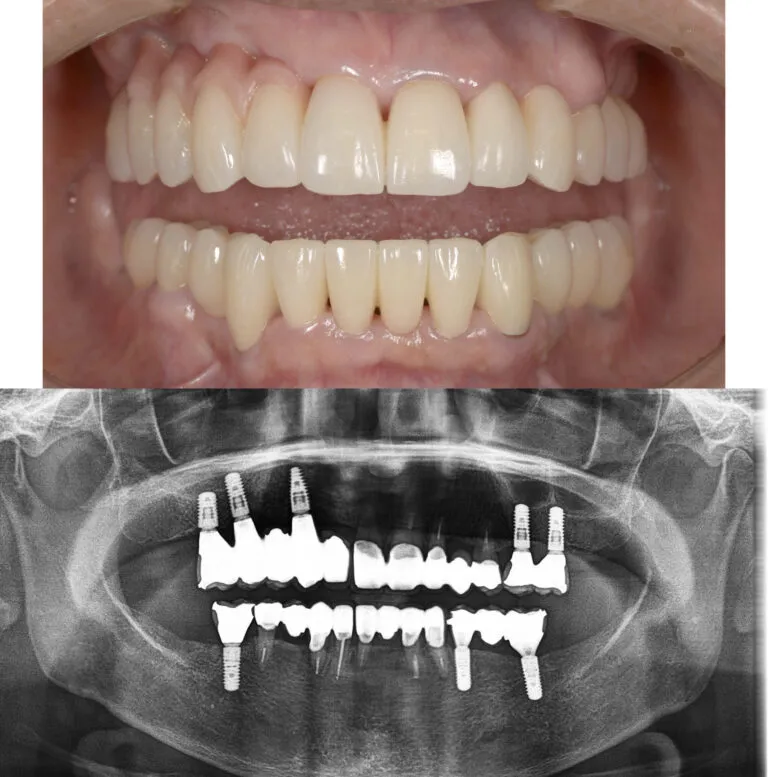

症例3

- 主訴

- 歯が揺れている。全体的な治療を希望

- 治療内容

- インプラント治療、セラミックによる補綴治療

- 治療費

- 450万

- 治療期間

- 1年6ヶ月

- 通院回数

- 50回

- 想定されたリスク

- 将来的な二次カリエス、歯周病の悪化

- コメント

- 入れ歯を使用せずに、しっかり噛めるようになりたいという希望を達成することができました。

before

after